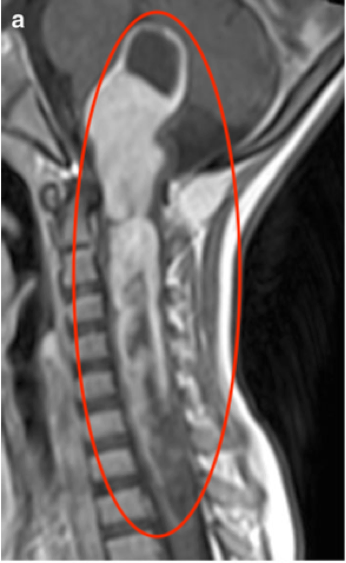

体格检查显示步态共济失调明显,左侧面部V2和V3分布区感觉明显...